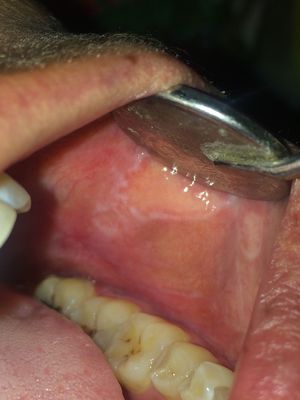

whts the DD??

burnng sensation.. young female patient 27 year of age

Stomatitis aftosa?

present on both sides..

Oral lichen planus...?